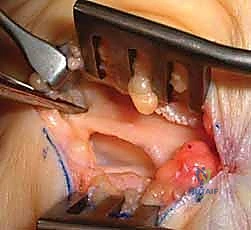

- الأمام (السقف): يتكون من شريط ليفي سميك، قوي جداً، وغير مرن يُعرف باسم الرباط الرسغي المستعرض (Transverse Carpal Ligament - TCL)، أو القيد القابض (Flexor Retinaculum). هذا الرباط هو الهدف الرئيسي في عملية "تحرير النفق الرسغي"، حيث يتم قطعه لتوسيع النفق.